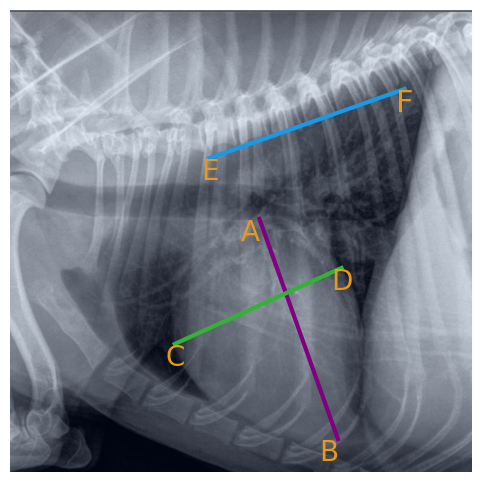

• Let A𝐴Aitalic_A, B𝐵Bitalic_B, C𝐶Citalic_C, D𝐷Ditalic_D, E𝐸Eitalic_E, and F𝐹Fitalic_F represent specific anatomical points within the X-ray, predicted by the model output f(x)𝑓𝑥f(x)italic_f ( italic_x ).

VHS=6AB+CDEF,VHS6𝐴𝐵𝐶𝐷𝐸𝐹\text{VHS}=6\cdot\frac{AB+CD}{EF},VHS = 6 ⋅ divide start_ARG italic_A italic_B + italic_C italic_D end_ARG start_ARG italic_E italic_F end_ARG , (3)

where AB𝐴𝐵ABitalic_A italic_B and CD𝐶𝐷CDitalic_C italic_D represent the long and short axes of the heart, and EF𝐸𝐹EFitalic_E italic_F represents the length of the vertebral segment. The factor of 6 is applied to scale the ratio in line with veterinary standards for VHS measurement.

The anatomical landmarks AB𝐴𝐵ABitalic_A italic_B, CD𝐶𝐷CDitalic_C italic_D, and EF𝐸𝐹EFitalic_E italic_F, used for VHS computation, are visually illustrated in Figure 2. Here, AB𝐴𝐵ABitalic_A italic_B represents the heart’s long axis, CD𝐶𝐷CDitalic_C italic_D is the short axis, and EF𝐸𝐹EFitalic_E italic_F corresponds to the vertebral segment, which provides the normalization factor.

Figure 2: Illustration of anatomical landmarks for VHS calculation. AB𝐴𝐵ABitalic_A italic_B (long axis), CD𝐶𝐷CDitalic_C italic_D (short axis), and EF𝐸𝐹EFitalic_E italic_F (vertebral segment) are shown, which are used to compute the Vertebral Heart Score (VHS).